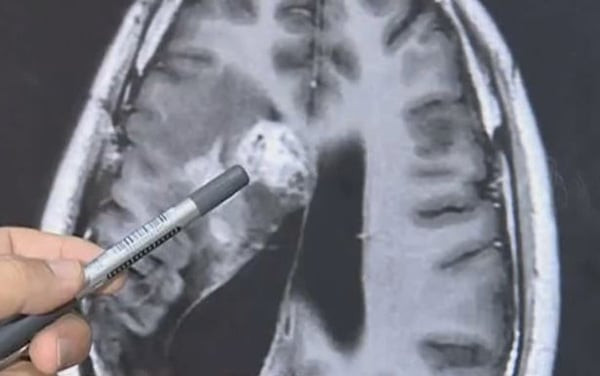

یونیورسٹی کی جانب سے رگبی، فٹبال اور باکسنگ کے سابق کھلاڑیوں کو مرنے کے بعد دماغ عطیہ کرنے کی درخواست کی گئی ہے۔ فوٹو: فائل

نیورولوجسٹ رچرڈ فائویل کنکشن پر ریسرچ کررہے ہیں، یونیورسٹی کی جانب سے رگبی، فٹبال اور باکسنگ کے ایسے سابق کھلاڑیوں کو مرنے کے بعد دماغ عطیہ کرنے کی درخواست کی گئی ہے جن پر کھیل کے دوران کبھی سر انجری کی وجہ سے غنودگی کی کیفیت طاری نہ ہوئی ہو،اس تحقیق کی روشنی میں چوٹ کے اثرات سے بچائوکی تدابیرہوں گی۔